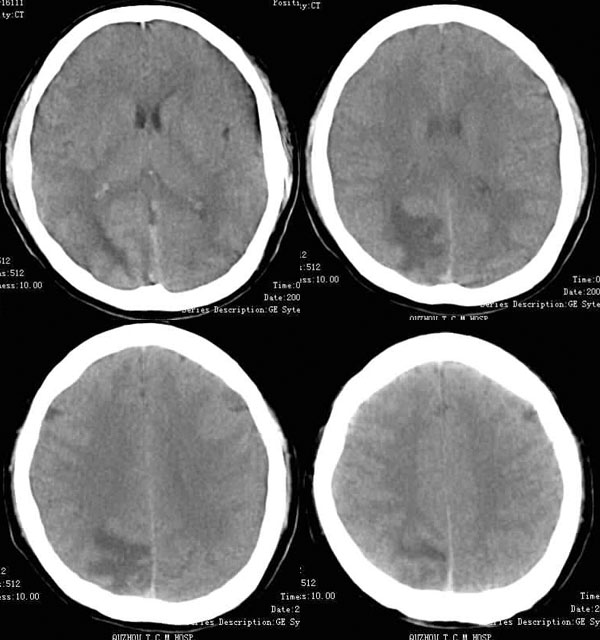

男.30岁.反复头痛半年.最近一星期加重.后边几幅是5mm扫描的

ct平扫:右顶叶可见大片指状水肿,边缘不清,其内后部似有一小环形略高密度影。

增强扫描:指状水肿不强化,其内后部有一圆形厚壁强化环,内壁光滑,外壁较毛糙,占位不明显。

结合临床,考虑右顶叶结核瘤并发结核脓肿。

应与化脓性脑脓肿鉴别,化脓性脑脓肿发病率高,进展快,灶周水肿轻,而结核性脓肿较少见,通常肿脓壁较厚,灶周水肿明显,常与脑膜炎或(和)结核瘤并存。鉴别诊断必须密切结合临床。本例病人病程长,进展慢,灶周水肿明显。